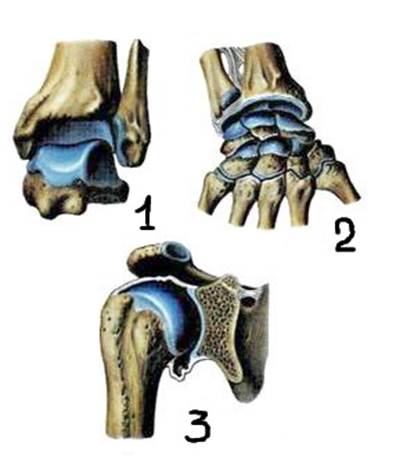

Структура и анатомия синдесмоза: научные иллюстрации